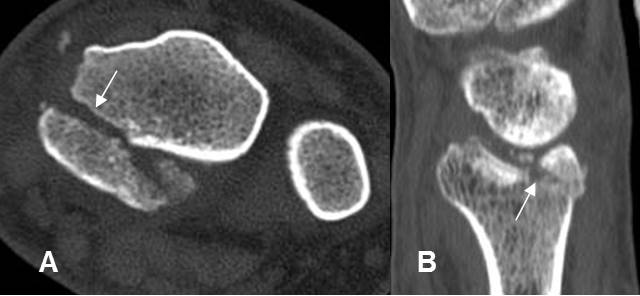

A: TAC axial y B: TAC reconstrucción sagital. Fractura intra-articular, que compromete la parte posterior del radio.